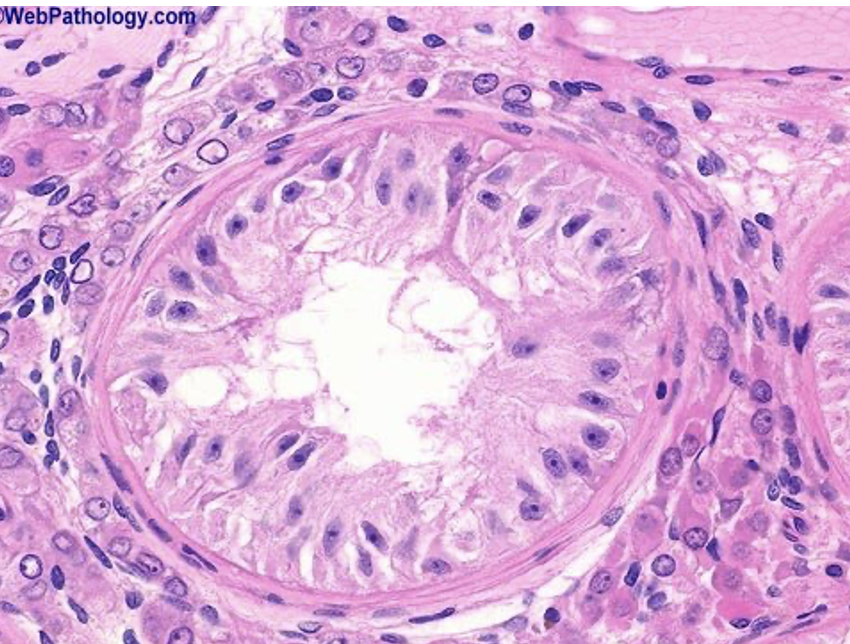

Biopsy of a testis under the microscope

-You can see the Leydig cells surrounding the seminiferous tubules but it is more sparse because there is a little bit of oedema fluid surrounding the outside of the seminiferous tubule and this also might be caused by the process of taking the biopsy.